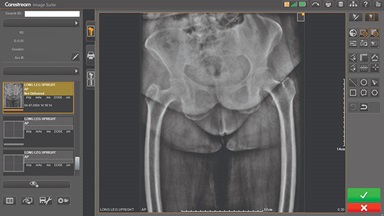

Carestream Introduces New Software Update to Boost Diagnostic Accuracy

Carestream today announced the latest update to its Image Suite V4 Software, MR 11: a series of enhancements to help improve customer confidence and increase diagnostic accuracy [...]

CARESTREAM Image Suite V4 MR11 has set a new standard for workflow efficiency, offering a robust set of features and functionalities to enhance clinical confidence in healthcare professionals. Using an auto-generated companion image from a single exposure, leverage a range of image processing options to increase diagnostic accuracy and enhance patient care.